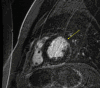

Anomalous left coronary artery to pulmonary artery (ALCAPA) is a leading cause of pediatric myocardial ischemia. This paper presents a case of a young man presenting with ventricular tachycardia storm 18 years after ALCAPA repair. Clinicians should recognize the risk of ventricular tachycardia in this patient population.